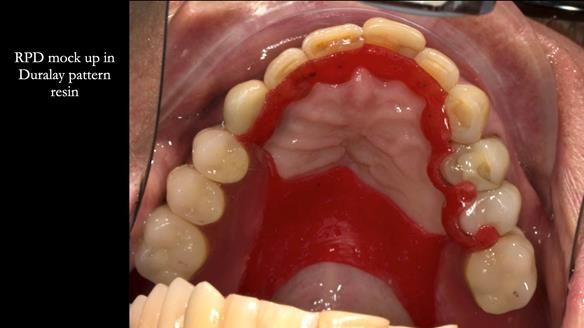

The upper jaw

In the upper arch:

- a failing upper left tooth supporting a bridge was removed

- an implant-supported bridge on the upper right was dismantled

A metal-based upper RPD was made,

with metal backings incorporated to future-proof the design

should further teeth fail.

The way Rowan lengthened the teeth — particularly in the upper RPD — to match the existing gingival recession on the remaining teeth was superb. The dentures sit naturally within the context of the rest of the mouth.